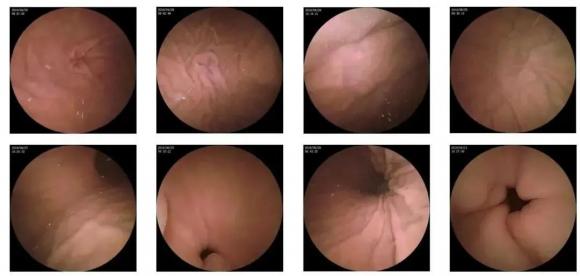

10—15分鐘即可完成賁門、胃底、胃體、胃角、胃竇、幽門等解剖部位觀察,讓胃部檢查更高效。更為重要的是,檢查全程無痛、無創、無麻醉,避免了傳統插管胃鏡帶來的生理痛苦。

二、高清圖像,精確診斷

膠囊機器人的專利三鏡片鏡頭,可深入觀察0.04毫米微小單位,每秒可拍高達4張高清醫學照片。

醫生通過智能閱片系統,可自動對海量圖像識別過濾,智能篩選,能有效提升醫生檢查及閱片效率。

任何細微的胃部病變,如胃潰瘍、胃出血、息肉等都無所遁形,盡在大圣磁控膠囊式內窺鏡系統的掌握之中。